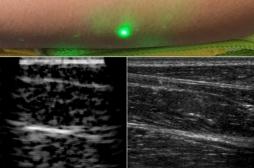

échographie

EN DIRECT